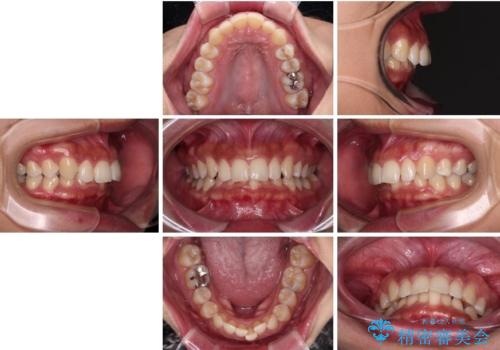

抜歯矯正で口が閉じやすく|ディープバイトと叢生を改善した症例

- 下顎前歯部には叢生が認められ、口を自然に閉じにくい状態でした。また、噛み合わせが深い「ディープバイト」の状態で、見た目だけでなく将来的な奥歯への負担も懸念されました。

口元の突出感を改善するため、上下左右の小臼歯4本を抜歯する矯正治療を計画しました。